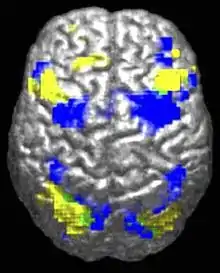

При анализе работы мозга лиц с расстройствами аутистического спектра паттерны сниженной и аберрантной активации различаются в зависимости от того, какую задачу выполняет испытуемый — социальную или не-социальную.[85] Существуют свидетельства того, что при аутизме нарушена функциональная связность сети пассивного режима работы мозга (англ. default network), обширной системы взаимодействующих участков головного мозга, активной в состоянии, когда человек не занят выполнением какой-либо задачи, связанной с внешним миром, а, напротив, бездействует, отдыхает, грезит наяву или погружён в себя. В то же время сохранена связность сети оперативного решения задач (англ. task-positive network), играющей роль в поддержании внимания и целенаправленном мышлении. Отсутствие негативной корреляции в активации двух сетей у аутистов предполагает наличие дисбаланса в переключении между ними, что может свидетельствовать о нарушениях самореферентного мышления.[86] При нейровизуальном исследовании работы поясной коры, проведенном в 2008 году, у лиц с расстройствами аутистического спектра был обнаружен специфический паттерн активации этой части мозга.[87]

Согласно теории недостатка связности, при аутизме может быть снижена функциональность высокоуровневых нейрональных связей и синхронизации при избытке низкоуровневых процессов.[90] В пользу теории говорят данные фМРТ-исследований[31] и результаты одного исследования волновой активности, позволяющего предположить избыток локальных связей в коре и ослабленную функциональную связность лобной доли с другими областями коры.[91] В других работах предполагается, что недостаток связности преобладает внутри полушарий и аутизм представляет собой расстройство ассоциативной коры.[92]